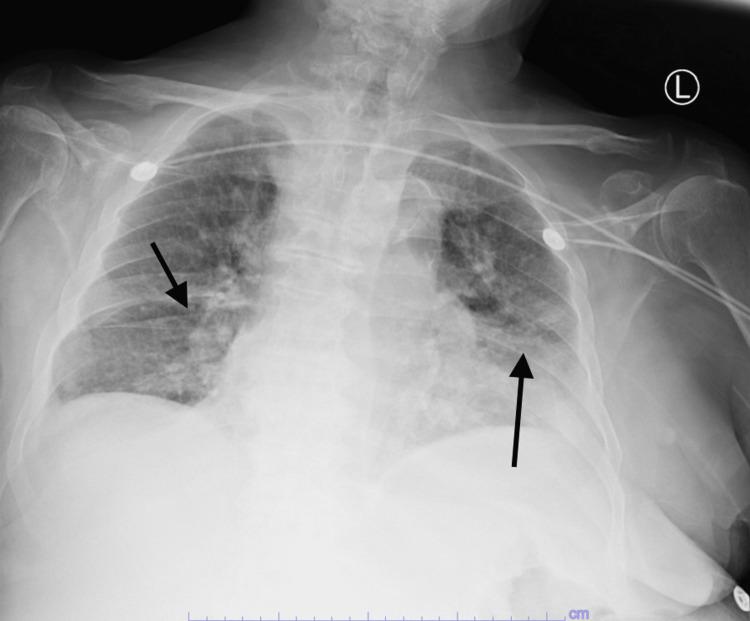

Coronavirus disease 2019 (COVID-19) is caused by severe acute respiratory syndrome coronavirus 2 (SARS-CoV-2) and can be a plausible trigger for both disseminated intravascular coagulopathy (DIC) and acute pancreatitis. We present an 85-year-old male patient who presented with altered mental status and tested positive for COVID-19 infection. He was hypoxic with an incremental need for oxygen. He had clinical as well as imaging evidence of acute pancreatitis. Clinical evidence of bleeding was noted and lab findings were suggestive of DIC. Despite aggressive initial management, his clinical status continued to deteriorate and comfort care was sought eventually. This case highlights COVID-19 infection as a possible trigger for acute pancreatitis as well as DIC. It also highlights some of the differences in COVID-19-induced DIC, which fulfills the diagnostic criteria of DIC but has atypical findings.

2019冠状病毒病(COVID-19)由严重急性呼吸综合征冠状病毒2(SARS-CoV-2)引起,可能是弥散性血管内凝血(DIC)和急性胰腺炎的一个合理触发因素。我们报告一名85岁男性患者,其出现精神状态改变,COVID-19感染检测呈阳性。他存在缺氧情况,且对氧气的需求不断增加。他有急性胰腺炎的临床及影像学证据。注意到有出血的临床证据,实验室检查结果提示存在DIC。尽管最初进行了积极治疗,但其临床状况仍持续恶化,最终寻求了舒适护理。该病例突出了COVID-19感染作为急性胰腺炎以及DIC的一个可能触发因素。它还突出了COVID-19诱导的DIC的一些差异,这种DIC符合DIC的诊断标准,但有非典型表现。